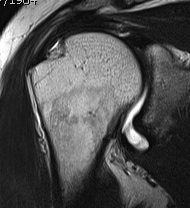

MRI

Articular Sided / PASTA (partial articular sided tendon avulsion)

Bursal Sided